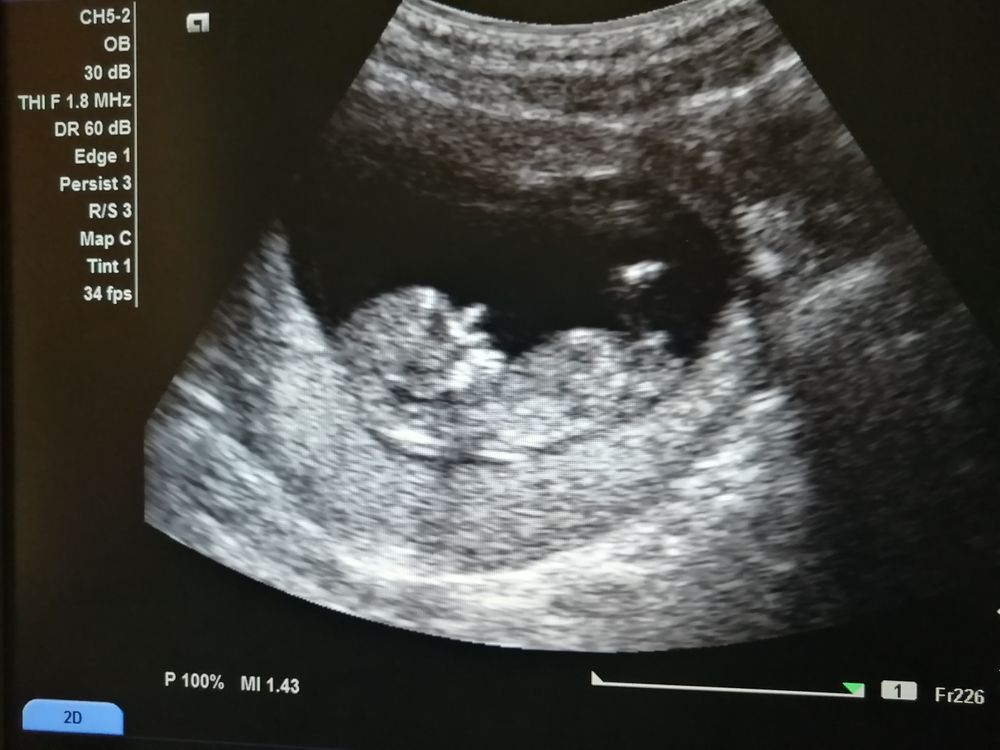

Мой первый скрининг

Вот я и сходила на первый скрининг. По УЗИ все в пределах нормы. Меня правда смущает нос 😃, как у Буратино.

Пол сказали "сложно сказать, но похоже на девочку". А вы как думаете? Фото не получается добавить. В комментариях будет

Ахаха)))) Носик как раз аккуратный))) То, что можно принять за нос - скорее всего пальчики от руки виднеются сбоку (явно обе ручки подняты вверх, так лежит малыш просто)))

Пока на девочку больше похоже. В 20-21 недели будет видно окончательно. Можно смотреть начинать с 16-17 недели, если не хочется ждать, но чтобы прибор в клинике был нормальный. Тут на снимке тоже не самая лучшая четкость у прибора на лицо. А носик - это так ручки лежат у головы, у лица)